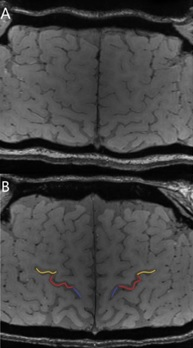

47 ALS patients, 23 healthy controls (HC), and 15 ALS Mimics (ALS-Mim) were retrospectively recruited. Among the ALS patiens, 12 with predominant UMN impairment (UMN-ALS), 16 with predominant LMN imparment (LMN-ALS), and 19 with no clinically-defined predominance (c-ALS). MRI scans were performed in a 3T SIGNA General Electric unit and included: 3D sag FSPGR BRAVO T1-weighted images (TR=8.7 ms, TE=3.2 ms; TI=450 ms; voxel size=1x1x1 mm, flip angle=12°; matrix 256x256); 3D spoiled gradient-echo multi-echo pulse sequence (TR=39 ms; 7 echoes with TE1=24 ms and ΔTE=3.3 ms; voxel size=0.468x0.468x1.4 mm; flip angle=20°; matrix 416x320). The visual assessment was performed by the Motor Cortex Susceptibility (MCS) score based on the visual inspection of the SWI hypointensity in the precentral cortex [6] shown in Fig. 1, a-b. The automatic assessment was performed by Freesurfer segmentation, quantitative susceptibility mapping (QSM) using STI Suite (Fig. 2) and computation of the skewness of the susceptibility values in the precentral cortex (SuscSkew) [4].

Motor cortex segments visually assessed by the Motor Cortex Susceptibility (MSC) score in Susceptibility-weighted imaging (SWI)